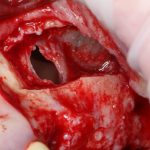

Кстати, обрати внимание на ширину альвеолярного гребня (левая картинка). Она чуть меньше 3 мм. Это объясняет, почему я засомневался в возможности установки имплантатов одновременно с остеопластикой. Понятно и без КЛКТ.

Наперво, мне нужно удалить разрушенный зуб и получить костный аутотрансплантат.